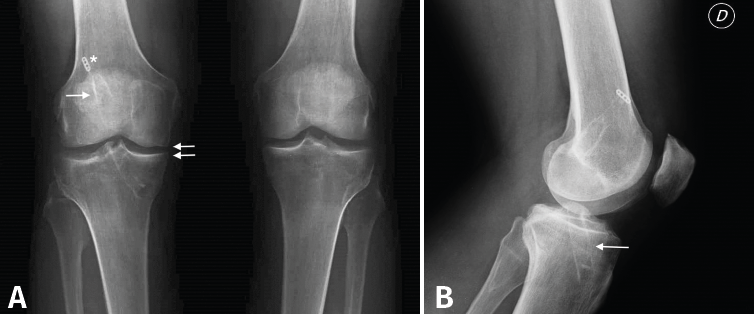

Figura 1. A: radiografía anteroposterior de ambas rodillas en carga. Se puede apreciar, en la rodilla derecha, el túnel femoral de la plastia del ligamento cruzado anterior (LCA) muy verticalizada (flecha), así como el dispositivo de suspensión de fijación femoral (estrella). Se aprecian signos incipientes degenerativos en el compartimento medial (doble flecha); B: radiografía lateral de rodilla derecha en la que se aprecia túnel tibial en posición posterior a la que correspondería a la situación anatómica del LCA.

En las pruebas complementarias actualizadas presentaba, en las radiografías simples (Rx) anteroposteriores en carga de ambas rodillas (Figura 1A), un túnel femoral muy vertical, con un dispositivo de suspensión como material de fijación y algunos cambios degenerativos incipientes en el compartimento medial. En la Rx lateral de rodilla (Figura 1B) presentaba un túnel tibial muy posterior. En la resonancia magnética (RM) (Figura 2), persistía la integridad de la plastia inicial del LCA, además de los hallazgos descritos en las Rx, así como una meniscectomía amplia.